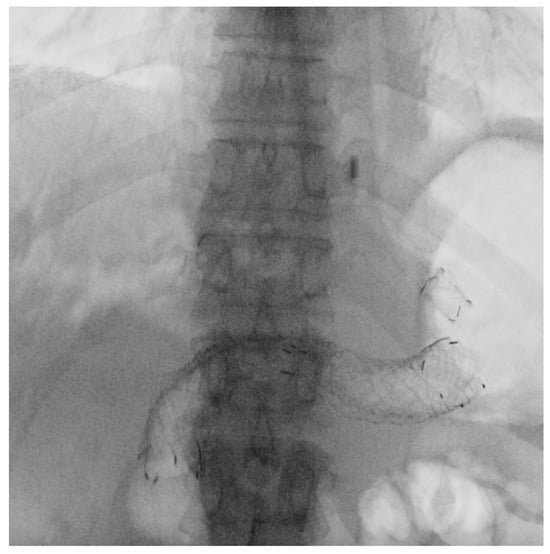

3.2.2. EUS-HGS